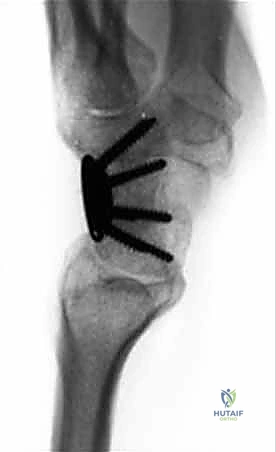

يتم الإجراء عن طريق إزالة الغضاريف التالفة بين عظام معينة في الرسغ (عادةً تلك التي تعاني من أقصى درجات الاحتكاك والتهاب المفاصل)، ثم وضع طعوم عظمية بينها وتثبيتها باستخدام مسامير أو شرائح معدنية دقيقة. بمرور الوقت، ينمو العظم الجديد ليلحم هذه العظام معاً لتصبح كتلة عظمية واحدة صلبة (Fusion).

* الآلية: يتم استئصال "العظم الزورقي" (Scaphoid) بالكامل لأنه يكون غالباً مصدر المشكلة والألم. بعد ذلك، يتم دمج العظام الأربعة المتبقية في المركز معاً: العظم الهلالي (Lunate)، العظم الكبير (Capitate)، العظم الكلابي (Hamate)، والعظم المثلثي (Triquetrum).

في حالة دمج الزوايا الأربع، يتم استئصال العظم الزورقي بالكامل. بعد ذلك، تأتي الخطوة الأكثر أهمية وهي "إزالة القشرة المفصلية" (Decortication). باستخدام أدوات دقيقة جداً، يتم تقشير الغضاريف التالفة من الأسطح التي سيتم دمجها (العظم الهلالي، الكبير، الكلابي، والمثلثي) وصولاً إلى العظم الإسفنجي النازف الذي يحتوي على الخلايا الجذعية وعوامل النمو الضرورية للالتئام.